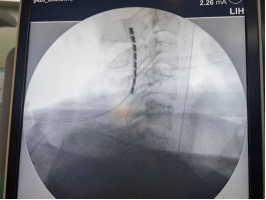

手术中骨科刘晓东副主任医师用C臂机定位电极植入位置

脊髓电刺激作为一种新型有效的植物人促醒技术,通过在高位颈髓植入电极,脉冲式放电由脊髓传入大脑,增加大脑血流量,激活神经系统,改善脑循环,兴奋大脑皮层,达到促醒的目的。经过缜密的术前准备,郭冕教授带领团队成功将刺激电极安置在患者颈2-4硬脊膜外,以增强脑干网状激活系统起始部意识冲动的输入,实现促醒。手术一周后顺利开机,目前宋先生电刺激反应良好,意识状态得到显著的改善。

植入的电极

电极植入成功